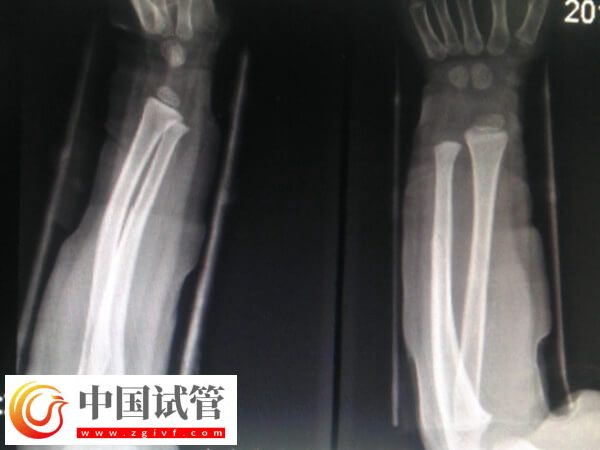

骨折愈合一年可不可以做试管

患者骨折愈合一年之后一般是可以做试管婴儿的,这时骨折部位已经基本恢复稳定,身体也基本恢复到正常状态,所以不会对试管婴儿的整个流程产生直接的不良影响。不过为了确保妊娠的安全性,建议患者一定要注意观察身体状态,以及骨折位置,若是有任何异常,则建议及时就医,以提高试管妊娠成功率。

骨折过的人,多数能够恢复到原来正常水平一样。因为大多数的骨折都可以得到及时的正确的复位,都能恢复到原来正常水平一样。所以骨折愈合一年后是可以做试管婴儿的,但为了确保骨折位置和妊娠的安全性,建议患者还要注意以下几点事项。